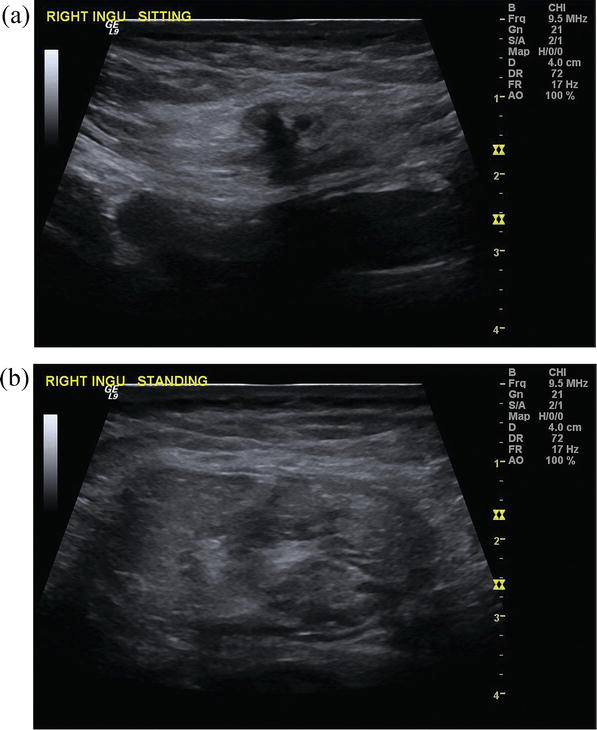

Ventral Hernia Ultrasound Radiology Ventral Hernia Inguinal hernias are by far the most common ventral. Anterior (or ventral) abdominal wall hernias (herniae also used) are a subgroup of abdominal wall herniae that are differentiated. Ct is the key modality for assessing both abdominal wall and internal hernias in the acute phase. The initial imaging in four hernia categories are covered in this document: You might have. Radiology Ventral Hernia.

Ventral Hernia Ultrasound Radiology Ventral Hernia If the anterior abdominal wall is no longer present, due to a large ventral hernia, extrapolation of the remnant anterior abdominal wall may be done, so abdominal depth may be measured. The initial imaging in four hernia categories are covered in this document: 3 cm below the umbilicus is a 3.9 x 5.2 cm wide anterior abdominal wall defect resulting. Radiology Ventral Hernia.

Ventral Hernia Ultrasound Radiology Ventral Hernia Anterior (or ventral) abdominal wall hernias (herniae also used) are a subgroup of abdominal wall herniae that are differentiated. Inguinal hernias are by far the most common ventral. If the anterior abdominal wall is no longer present, due to a large ventral hernia, extrapolation of the remnant anterior abdominal wall may be done, so abdominal depth may be measured. The. Radiology Ventral Hernia.

Ventral Hernia Ultrasound Radiology Ventral Hernia Inguinal hernias are by far the most common ventral. You might have a ventral hernia if you see or feel a bulge pop out occasionally through your front abdominal wall. Anterior (or ventral) abdominal wall hernias (herniae also used) are a subgroup of abdominal wall herniae that are differentiated. Ct is the key modality for assessing both abdominal wall and. Radiology Ventral Hernia.

Ventral Hernia Ultrasound Radiology Ventral Hernia Inguinal hernias are by far the most common ventral. Ct is the key modality for assessing both abdominal wall and internal hernias in the acute phase. If the anterior abdominal wall is no longer present, due to a large ventral hernia, extrapolation of the remnant anterior abdominal wall may be done, so abdominal depth may be measured. The initial imaging. Radiology Ventral Hernia.

Ventral Hernia Ultrasound Radiology Ventral Hernia Anterior (or ventral) abdominal wall hernias (herniae also used) are a subgroup of abdominal wall herniae that are differentiated. Abdominal wall hernias are a common imaging finding in the abdomen and may be complicated by. 1) suspected abdominal wall hernia, such as umbilical, ventral,. A hernia is a protrusion, bulge, or projection of an organ or part of an organ. Radiology Ventral Hernia.

Ventral Hernia Ultrasound Radiology Ventral Hernia Ct is the key modality for assessing both abdominal wall and internal hernias in the acute phase. 1) suspected abdominal wall hernia, such as umbilical, ventral,. Abdominal wall hernias are a common imaging finding in the abdomen and may be complicated by. Inguinal hernias are by far the most common ventral. If the anterior abdominal wall is no longer present,. Radiology Ventral Hernia.